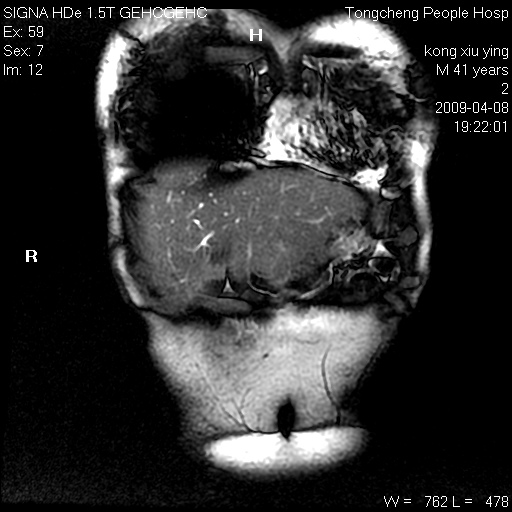

标题: CL1008:【经典】胆囊石榴籽样结石。

女,41岁。健康体检——彩超提示:胆囊显示不清。平素健康,无不适感。

腹部mr扫描及mrcp,图像如下: